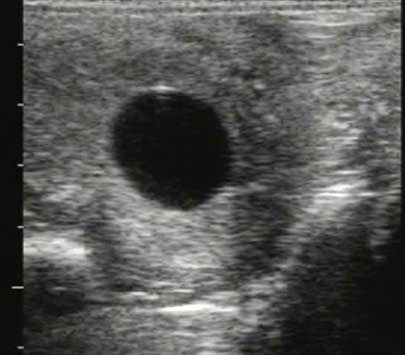

Se organiza el seguimiento según el ciclo y marcamos el momento más adecuado para actuar y no perder oportunidades. En todos estos procesos, la ecografía reproductiva es una herramienta de control indispensable.

En JRO Veterinario Equino trabajo con enfoque equino integral, que cubre las provincias de Huelva, Cádiz, Sevilla, Badajoz y el Algarve portugués, donde la reproducción asistida forma parte de mis servicios especializados junto a otras áreas clínicas de apoyo como son el diagnóstico por imagen.